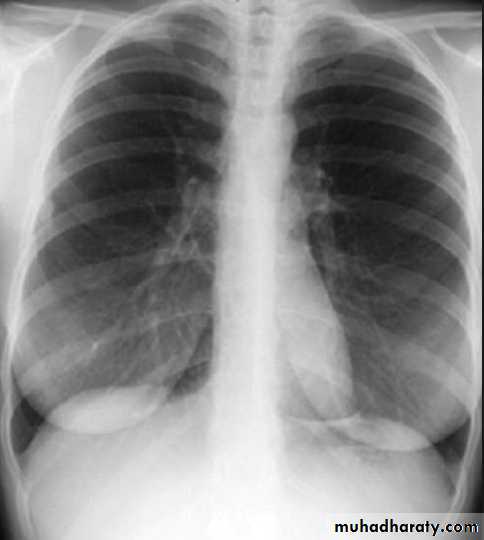

Both should exposed in full insp. And patient in upright position.Films taken in exp. Are difficult to interpret because:

• 1- hazy lung base.

• 2- heart shadow increase in size.

On good insp., the dome of rt. Hemidiaphragm at level of ant. End of 6th rib.